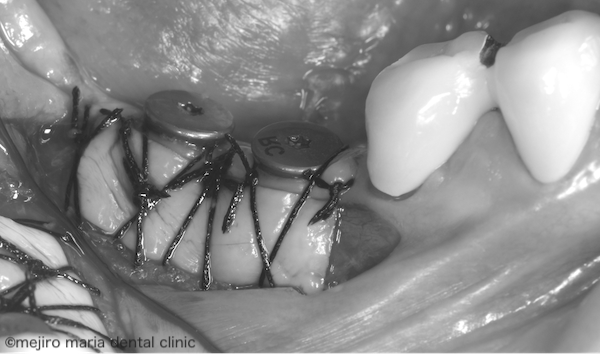

目白マリア歯科|歯周形成外科の症例|インプラントを守るための歯茎の移植(FGG)|治療中の歯茎の画像

歯肉の再生のために、上顎の口蓋にある硬いしっかりした歯肉を移植する手術を行いました。遊離歯肉移植術(FGG:Free gingival graft)と呼ばれる術式です。

インプラント周囲の付着歯肉の不足した部分に口蓋歯肉を移植し、しっかりと適合させます。すると、2週間もするとそこに移植片が生着し、硬い歯茎が形成されます。